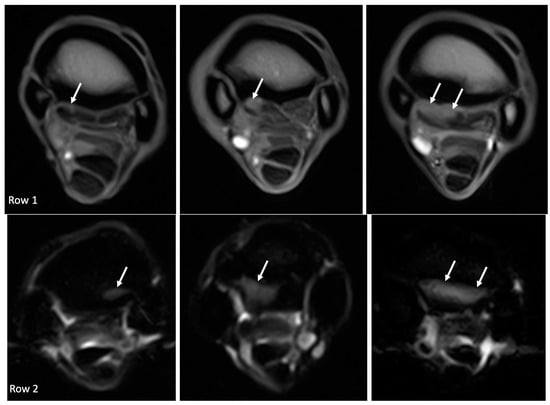

3. Results